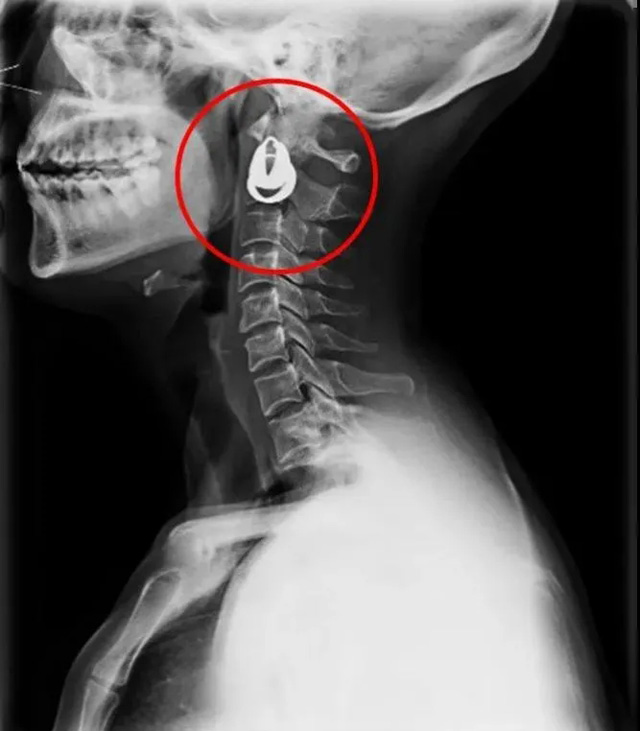

DR是一種比較常規(guī)的基礎影像學檢查方式,適用于人體各部位的健康普查及疾病檢查等優(yōu)勢,在臨床基礎檢查中備受醫(yī)生和患者的青睞。DR體檢車在健康體檢中有著非常重要的地位,由通過電纜串接在一起的探測板、掃描控制器、系統(tǒng)控制及影像顯示器等構成。對比CT檢查而言,DR檢查的價格更低,輻射劑量更小它可以讓疾病預防,微細病變可更好顯示診斷治療提供科學的結果依據(jù)。很多外傷患者都要做DR檢查,來判斷是否骨折或其他的情況。體檢過程中面對DR體檢車做檢查時候需要準備注意什么呢?很多時候大家都有這樣的疑問,身上攜帶的物品是否會對圖像造成遮擋或給機器帶來干擾?檢查前如何準備才不會影響檢查準確性?